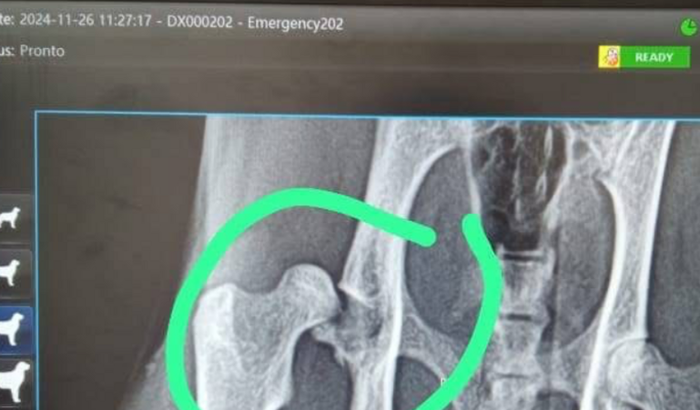

Me chamo jujuba, tenho 2 aninhos e na noite do dia 25/11 fui atropelada e a pessoa não prestou socorro, é isso resultou em várias fraturas no meu corpinho, na coluna, na cola, no fêmur e na bexiga, estou internada em uma clínica, pois as dores são muito fortes e fico 24h medicada para controle da dor, se eu não dizer a cirurgia rapidamente, as lesões irão se agravar e corro o risco de não andar mais!! Minha tutora (mamãe) está impossibilitada dessa quantia pois minha irmãzinha pipi acabou de retirar um câncer na mandíbula e não esperávamos por esse acidente comigo!